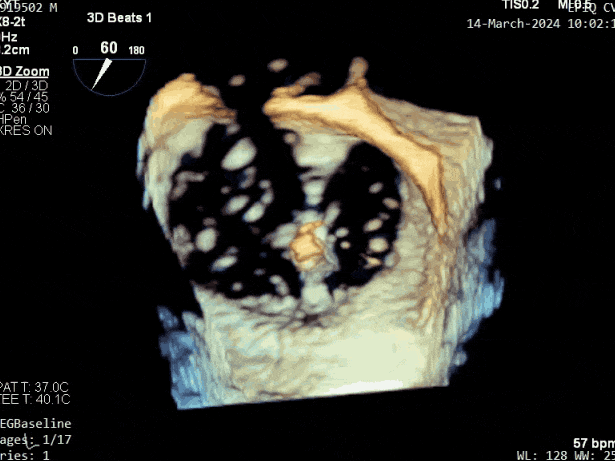

第三个瓣膜夹释放后评估,释放后评估,二尖瓣呈双孔,组织桥张力合适,瓣膜夹轴向与二尖瓣闭合线垂直,无残余反流

2. 本例患者外院超声心动图考虑二尖瓣前叶脱垂,入院后经食道超声心动图明确该患者为二尖瓣后叶活动受限,呈房源性栓系,二尖瓣前叶假性脱垂,超声特征表现为心房功能性二尖瓣反流终末期,呈现出很典型的二尖瓣后瓣环向左室游离壁顶部位移和后叶挛缩表现,同时合并有明显的二尖瓣瓣环扩张、圆形化,左房增大等不利因素,术中通过精准的影像指导和手术操作,成功行TEER,二尖瓣反流程度减轻至微量。